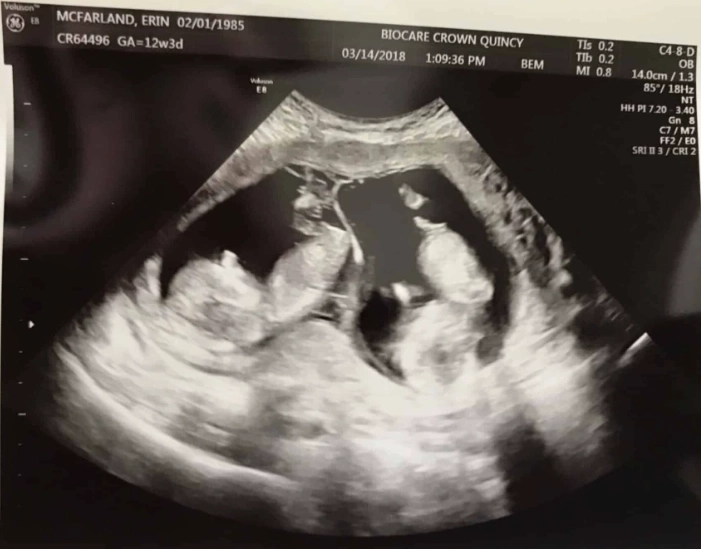

- Movement: Oh, they're moving! Kicking, stretching, even making little fist clenches. You won't feel it for several more weeks, but on an ultrasound, it's a beautiful, wiggly sight.

It's truly astonishing how much is accomplished in this first trimester. The Mayo Clinic provides excellent week-by-week details that reinforce just how dynamic this period is. Seeing this on a screen really drives home the reality of it all.

Q: Is it safe to announce my pregnancy at 12 weeks/3 months?

A: This is a deeply personal decision. Statistically, the risk of miscarriage does decrease significantly after the first trimester (which ends around 13 weeks). Many people feel more comfortable sharing the news after their 12-week scan. But there's no right or wrong time—do what feels right for you.

A: You've likely had initial blood work. The first-trimester screening, which can include a nuchal translucency ultrasound and blood tests (like the combined test), is typically done between weeks 11 and 14. This screens for certain chromosomal conditions. If you haven't discussed this with your provider, now is the time.